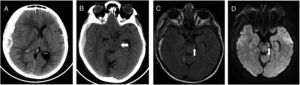

Brain CT showed extended right-sided subdural haematoma (A), with compression of left cerebral peduncle against free tentorial (B, white arrow). Brain MRI reveals a rounded hyperintense T2 FLAIR (C) and DW1 (D) images in left cerebral peduncle (white arrow), at 2 days after initial injury.

A 60-year-old woman, with past medical history of stroke (under treatment with aspirin and clopidogrel) presented with headache and incomplete palsy of III right cranial nerve. The patient referred a minor head trauma some days ago. Brain computed tomography (CT) showed an extended right-sided subdural haematoma (14mm), with mass effect, and midline shifted to the left (10mm) (Fig. 1). A craniotomy and evacuation of the subdural collection was done. The patient awaked confused, with right-sided hemiparesis. Cervical spine pathology and stroke were excluded. Magnetic Resonance Image (MRI) of the brain showed changes in the contralateral cerebral peduncle, compatible with Kernohan–Woltman notch phenomenon. She was transferred to the general ward with moderate right-sided hemiparesis.